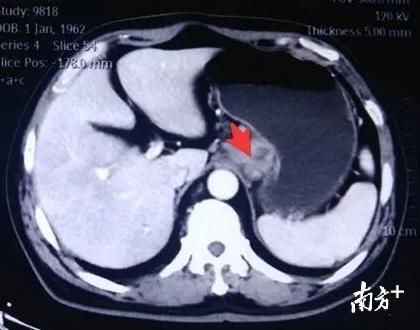

去年9月份,他的妻子看不下去了,拖着他到当地的一家大医院做了检查。检查结果让他非常沮丧——胃镜发现“贲门巨大溃疡”,进一步病理检查诊断为“低分化型、混合型贲门腺癌”,CT检查发现除贲门占位性病变外,“肝胃间隙及腹膜后多发肿大淋巴结”,考虑淋巴结转移,属于进展期的贲门癌。

在郑州,当地医院给陈先生做了2个疗程的化疗后,CT检查发现贲门病变部位有所好转,贲门壁增厚的情况有所改观,周围的肿大淋巴结也缩小了一些。

经过进一步认真细致的检查,CT发现贲门病变侵犯胃壁肌层,累及胃贲门后壁全层,病变周边、小网膜囊、脾胃间隙、肝门部、腹膜后等多发肿大淋巴结。凭借多年胃癌根治术及淋巴结脉络化清扫的经验,同时排除手术禁忌症,多学科讨论认为具备根治手术条件。